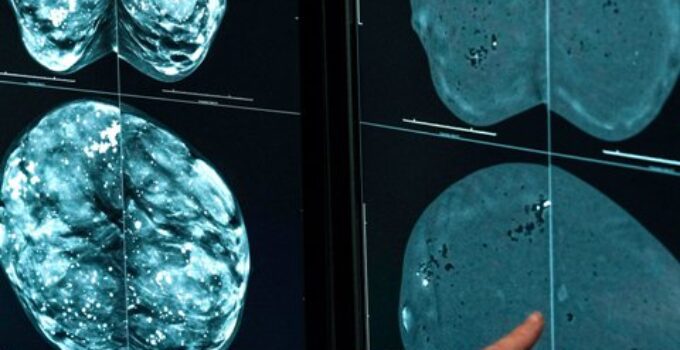

Mamografi, meme dokusunu özel bir röntgen cihazı ile görüntüleyen bir tanı ve tarama yöntemidir. Meme dokusu çok düşük dozda radyasyon kullanılarak iki plaka arasında hafifçe sıkıştırılır ve farklı açılardan görüntüler elde edilir. Bu sayede elle hissedilemeyen kitleler, mikrokalsifikasyonlar ve erken evre meme kanseri bulguları tespit edilebilir.